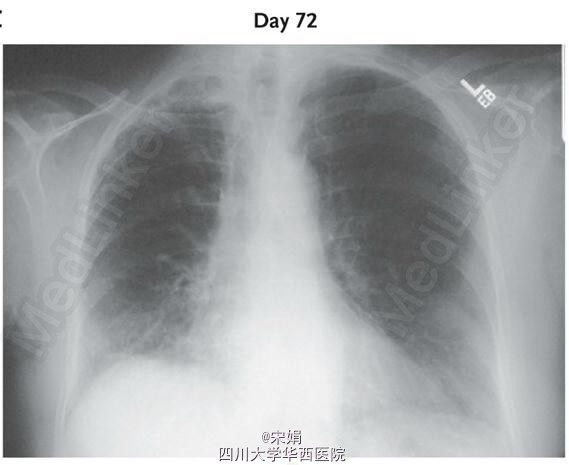

胸片发现不规则模糊影,主要分布在右半胸(入院后第3、5天胸片),经治疗模糊影明显消退(第72天胸片)。

使用一个肺音记录器来采集肺部14个部位的呼吸音,肺音分析结果用三维模型展示,形成动画和音频,如图绿色原点所示的爆裂音位置与胸片上右胸模糊影的位置相照应。治疗后爆裂音的数量也明显减少。